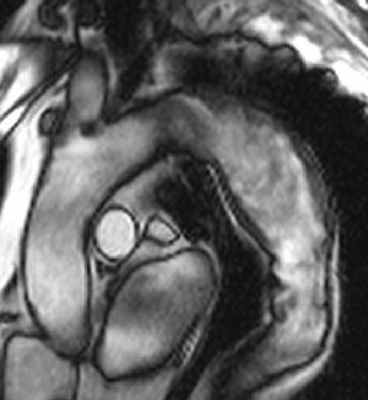

Рисунок 3. МРТ. Четырехкамерное сечение сердца. Апикальная гипертрофия миокарда левого желудочка.

- кардиомиопатии (аритмогенная дисплазия правого желудочка, дилатационная кардиомиопатия, гипертрофическая кардиомиопатия, синдром некомпактного миокарда). Под кардиомиопатиями понимают первичные заболевания миокарда после исключения клапанных, перикардиальных и коронарных болезней. МРТ помогает разграничить ишемическую и неишемическую дилатационную кардиомиопатию. МРТ является инструментом для визуализации редких расположений гипертрофии: в правом желудочке, в апикальном сегменте левого желудочка. МРТ является одним из главных методов в выявлении аритмогенной дисплазии правого желудочка (АДПЖ). Главные признаки АДПЖ на МРТ: локальное нарушение сократимости ПЖ, дилатация ПЖ, усиление трабекулярности ПЖ и отсроченное контрастирование миокарда ПЖ